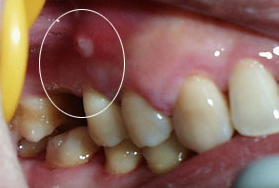

齿 牙妹,来看看这张照片?(图1 2)

齿 我的一个朋友,说最近牙龈不舒服,反复起小脓包,有时候就用针把脓包刺破,在用些碘伏局部涂抹消毒,可是没过多久又会再次长出脓包。

牙 嗯,脓包附近的牙齿有没有什么不舒服呢?

齿 他说曾经疼过,自己吃了些消炎药就挺过去了,后来牙齿的不适也减轻了,不过牙龈开始反复起脓包。牙妹,你的意思是---脓包可能来源于曾经疼痛过的牙齿?